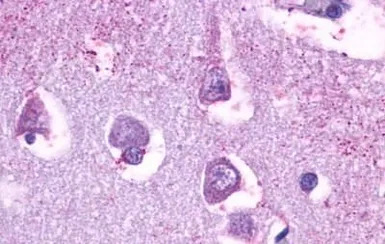

IHC-P analysis of human brain, neurons and glia tissue using GTX77997 5-HT5A receptor antibody.

Antigen retrieval : Heat-induced antigen retrieval